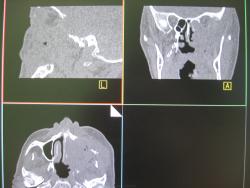

Каюсь гистологию даже не смотрел засмотрелся на картинку. Да изначально была гайморова пазуха. Затем после лучевой терапии на фоне ухудшения решили сделать КТ благо сейчас появилась такая возможность. И вот прорастание в глазницу с разрушение нижней её стенки, в носовую, ротовую полости, в среднюю черепную ямку. В общем все бесполезно...

Есть деструкция костей -один из критериев. Гистология в пн. Возраст порядка 50 лет. В пн уточну